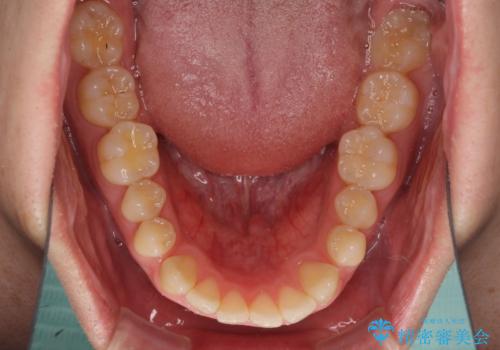

すきっ歯の改善 インビザライン矯正治療

インビザラインにより、上下の歯列を側方に拡大しつつ、前歯の隙間を閉じていくこととしました。

1日22時間の装着時間をしっかりと守ってくださったので、隙間がきれいに閉じ、口元の突出感も改善することができました。